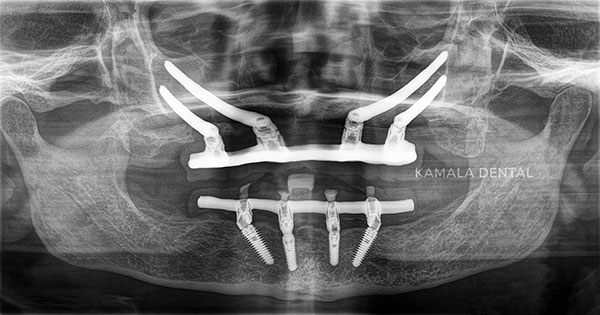

Full mouth implant supported dentures

Full mouth implants are an advanced dental solution designed to replace all missing or damaged teeth in the upper and/or lower jaws using dental implants. Instead of individual implants for each tooth, a few strategically placed implants support a full arch of artificial teeth, offering excellent stability and function. This treatment restores natural chewing ability, enhances facial appearance, and provides a long-lasting alternative to traditional dentures. Full mouth implants look, feel, and function like natural teeth, helping patients regain confidence in their smile while preserving bone health and preventing further jawbone loss.